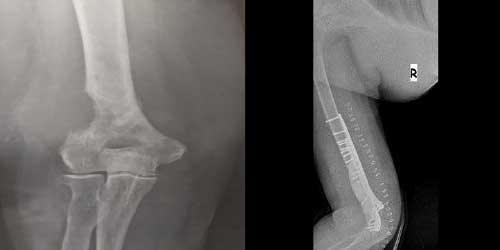

Her ameliyatın olduğu gibi kemik ve yumuşak doku tümör ameliyatlarının da riskleri vardır. Bu riskleri genel ve yapılan ameliyata özgü olmak üzere kabaca iki başlık halinde gruplandırabiliriz. Öncelikle anestezi ile ilgili risklerin anestezi uzmanı tarafından (...)

Ameliyat sonrası takip ve kontrol hastanın ameliyat masasında uyanması ile başlar. Özellikle damar ve veya siniri ilgilendiren ameliyatlarda hasta ameliyat masasından alınmadan ekstremitenin dolaşımı ve ilgili sinirin fonksiyonu kontrol edilir.